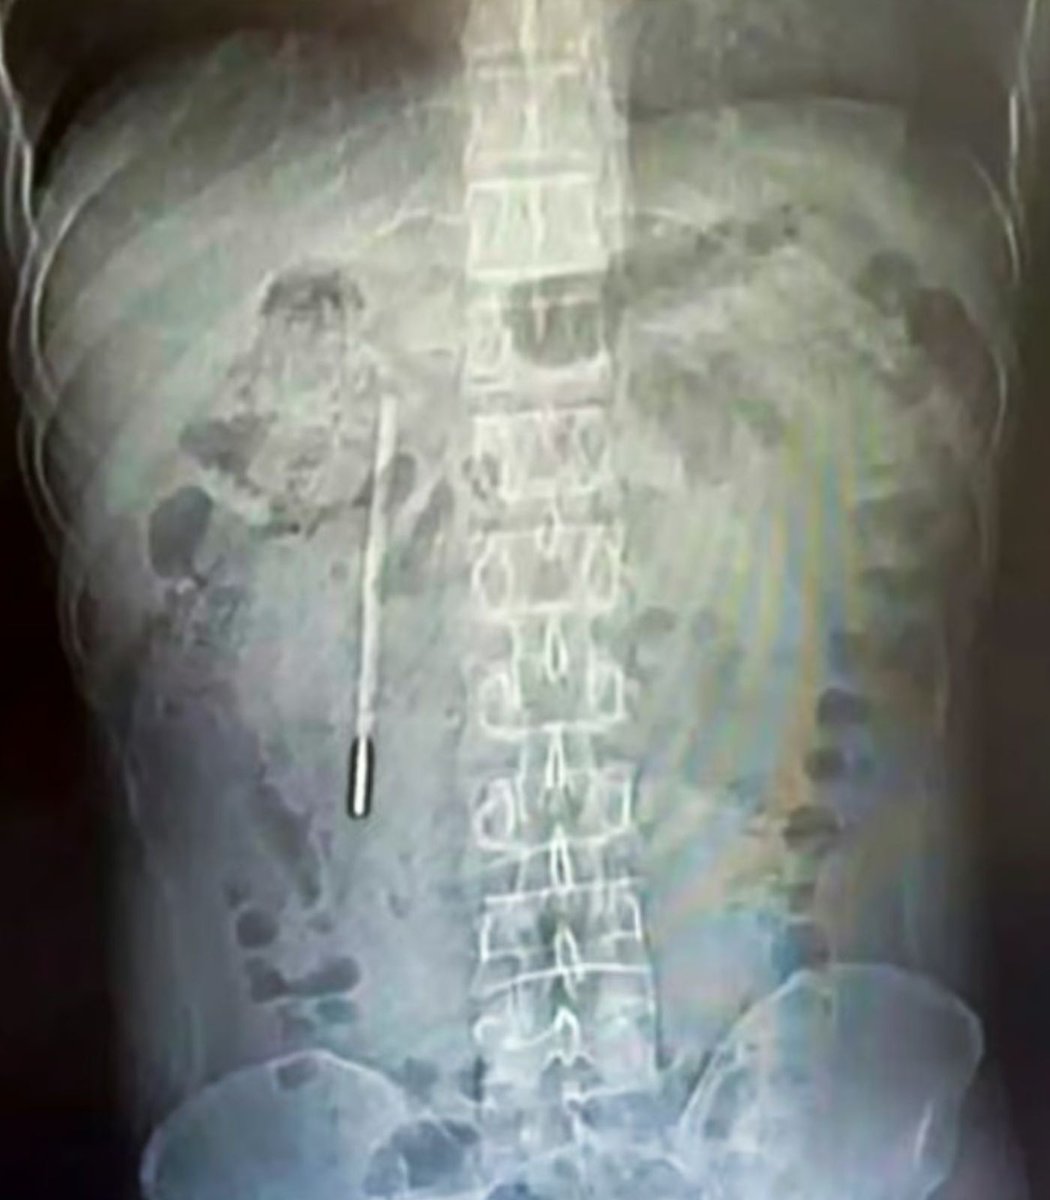

The research: jamanetwork.com/journals/jamap…